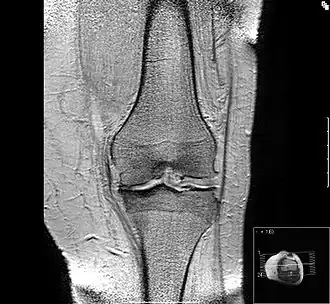

Нарушение оси нижней конечности при гонартрозе

Рентгенологическая семиотика остеоартроза складывается из признаков, отражающих дистрофические изменения в суставных хрящах (сужение суставной щели) и в костной ткани (уплощение и деформация суставных поверхностей, кистовидные образования), нестабильность суставов (подвывихи, искривления оси конечностей), реактивные компенсаторно-приспособительные процессы (краевые костные разрастания, субхондральный остеосклероз).